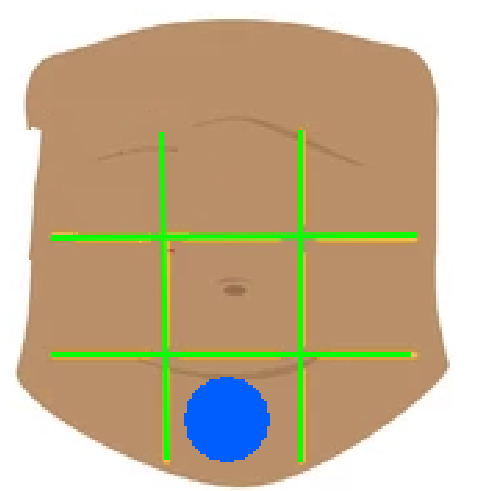

Right hypochondriac region

Left hypochondriac region

Epigastric region

Right lumbar region

Left lumbar region

Umbilical region

Right inguinal region

Left inguinal region

Hypogastric regions